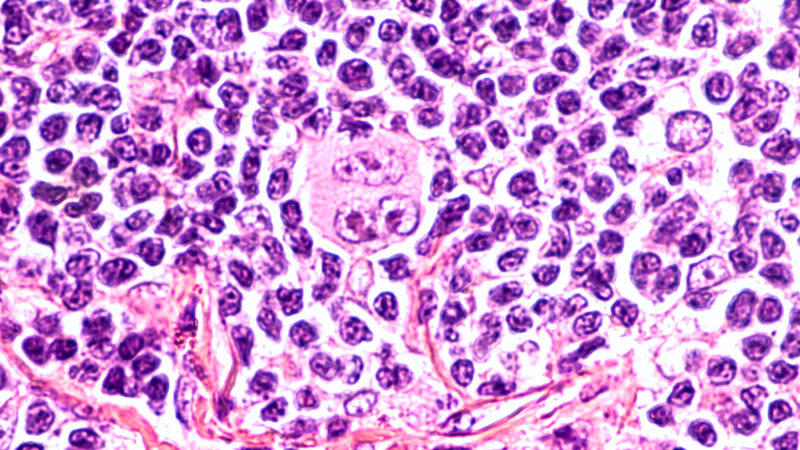

New research in the New England Journal of Medicine states that treatment with ibrutinib plus venetoclax (ABT-199) improved outcomes over standard therapy in patients with mantle-cell lymphoma (MCL) and a poor prognosis.

Currently, MCL is treated with targeted therapy for B-cell neoplasms, which includes ibrutinib, a BTK inhibitor, and venetoclax, an inhibitor of BCL2. Prior studies have reported that each has a complete response rate (CRR) of 21%. Preclinical models indicate that dual inhibition of BTK and BCL2 is synergistic. In addition, the agents have overlapping adverse events (AEs) that are generally minor.